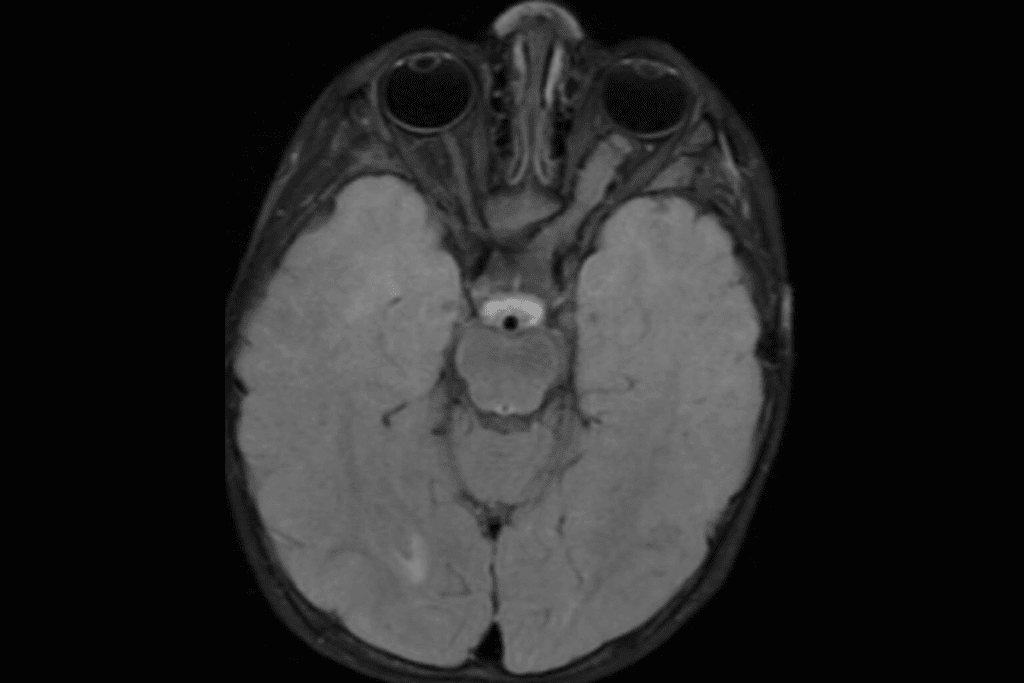

Imaging Tests: MRI, CT Scans, and More

Imaging tests are very important for finding brain tumors. The main tests are:

- MRI (Magnetic Resonance Imaging): Shows detailed brain images, helping find tumors and their size.

- CT Scan (Computed Tomography): Uses X-rays to see the brain, spotting tumors and other issues.

- PET Scan (Positron Emission Tomography): Shows how active the tumor is, helping in diagnosis and planning.

These tests are vital for pediatric oncology scans. They help doctors decide what to do next.